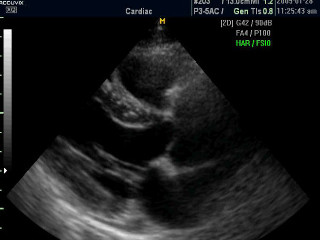

В современной медицине одним из наиболее информативных способов диагностики сердечных заболеваний наряду с ЭКГ, МРТ, КТ является – УЗИ. В процессе этой процедуры поток ультразвуковых волн, генерируемых датчиком аппарата УЗИ, направляют на исследуемый орган. Различные ткани организма по-разному поглощают, преломляют, отражают и рассеивают ультразвук. Отраженные, «вернувшиеся», волны регистрируются тем же датчиком, а их характеристики анализируются компьютером при помощи специальной программы в режиме реального времени. Результатом является визуализация полученных данных на мониторе. Так как общий принцип УЗИ строится на отражении волн, то УЗИ сердца называют ЭхоКГ (эхокардиография).

Процедура называется эхокардиографией, здесь применяется специализированная доплеровская приставка. Современные приборы позволяют оценить диагносту анатомическую конструкцию сердечной мышцы и сердечных клапанов, и оценить работу кровеносной системы.

- Второй вид — двухмерное ультразвуковое исследование. Показывает сердечную мышцу в двух измерениях. Врач получает возможность рассчитывать площадь отверстий митрального, аортального и трикуспидального сердечного клапана, и просвет магистральных сосудов.

- Ну и третий — трёхмерное УЗИ. Наиболее применимый сегодня способ исследования сердца. Даёт наиболее полную картину о кровообращении и анатомическом строении сердечной мышцы. На сегодняшний день диагностические аппараты предоставляют реальное изображение органа в объёме в режиме онлайн, что крайне благоприятно влияет на скорость постановки диагноза.